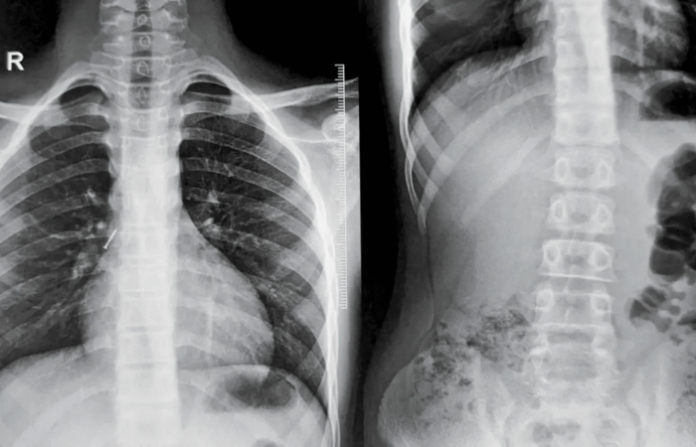

डॉक्टरांनी तात्काळ मुलाचा एक्स रे काढला. एक्स रे रिपोर्टमध्ये मुलाच्या फुफ्फुसाजवळ टाचणी असल्याचे आढळले. यानंतर कूपर रुग्णालयातील डॉ. शशिकांत म्हसाळ, डॉ. विनोद गीते, डॉ. अनिता शेट्टी यांच्या टीमने ‘रिजिड ब्रॉन्कोस्कोपी’ या अत्याधुनिक तंत्रज्ञानाचा वापर करून शस्त्रक्रिया केली. तोंडावाटे उपकरण आत टाकून, फुफ्फुसांचे वायुवीजन सुरळीत ठेवत अवघ्या 30 मिनिटांत ती टाचणी बाहेर काढली. वेळेत उपचार मिळाल्यामुळे मुलाच्या फुफ्फुसाचे मोठे नुकसान टळले असून त्याची प्रकृती आता स्थिर आहे.